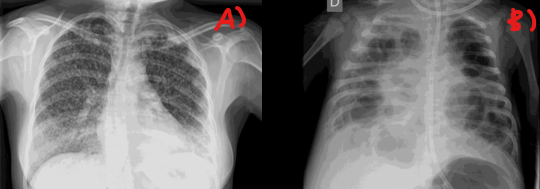

A)

B)

A) patrón miliar (muchos puntitos como alpiste)

B) patrón hiliar (cavernas)